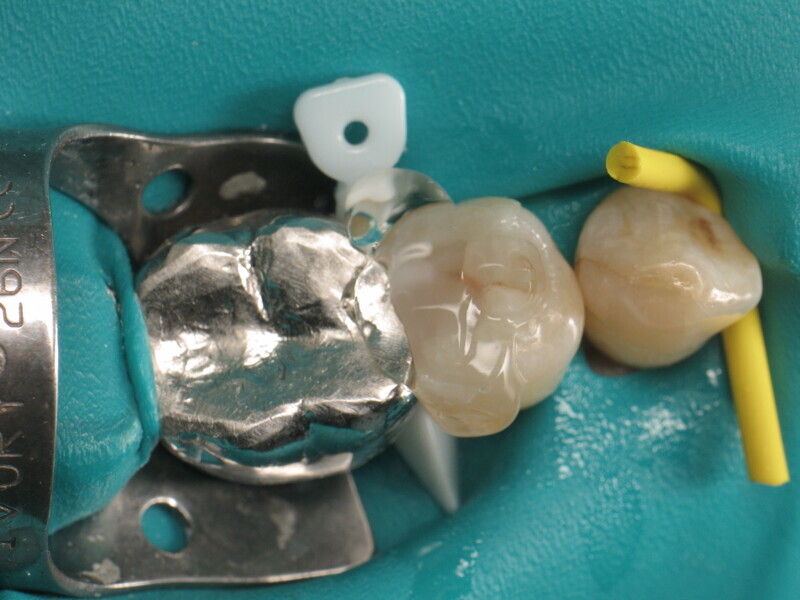

À l’aide du VisCalor Dispenser, un distributeur portatif permettant le chauffage et l’application simultanés de composites, la cavité est ensuite remplie d’un composite thermovisqueux bulk (VisCalor Bulk, A2, VOCO). L’utilisation d’un composite monocouche permet un remplissage rapide en une seule étape et peut être appliqué en couches allant jusqu’à quatre millimètres. Au fur et à mesure que le composite refroidit, sa viscosité augmente, ce qui le rend très facile à modéliser pour recréer l’anatomie et éliminer l’excès de matière (Fig. 12). Il est même possible de créer des sillons réalistes à l’aide d’une simple lime endodontique (Fig. 13).

Enfin, une photopolymérisation est réalisée pendant 20 secondes (puissance ≥ 1 000 mW/cm2 ; Fig. 14). Le maquillage est ensuite réalisé avec un composite teinté photopolymérisable (FinalTouch, VOCO, couleur orange, Fig. 15). Après 20 secondes de durcissement du composite de maquillage (Fig. 16), un gel de glycérine est appliqué (Fig. 17) puis la photopolymérisation finale est effectuée (Fig. 18). L’excédent est ensuite retiré et la surface est polie (Fig. 19). Pour ajuster l’occlusion, du papier à articuler est utilisé pour visualiser les points de contact (Fig. 20) et apporter les corrections nécessaires (Fig. 21). Le résultat final est très naturel (Fig. 22).